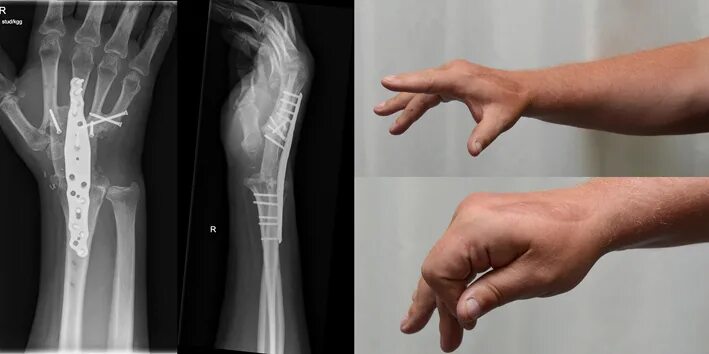

Перелом лучевой запястной кости. на переломе костную мозоль на лучевой кости. перелом лучезапястного сустава рентген. перелом лучевой кости рентген.

Остеосинтез перелома лучевой кости. оскольчатый перелом лучевой кости руки пластина. остеосинтез пластина при переломе лучевой кости. остеосинтез перелома лучевой кости пластиной.

Остеосинтез лучезапястного сустава. остеосинтез костей кисти. остеосинтез лучевой кости спицами. спицы киршнера рентген.